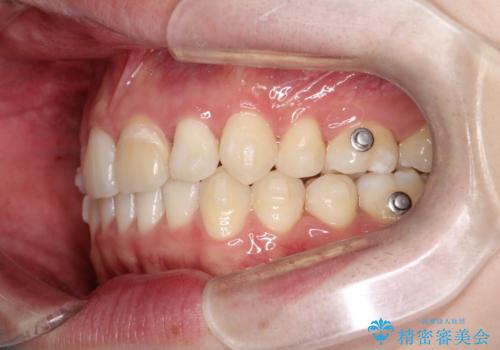

- 前歯が出ていることを主訴に来院されました。

臼歯関係が上顎前突傾向のため、上顎小臼歯を抜歯してインビザラインにて治療を行いました。

臼歯の咬合を作るために治療終盤ではゴムかけを行なっています。